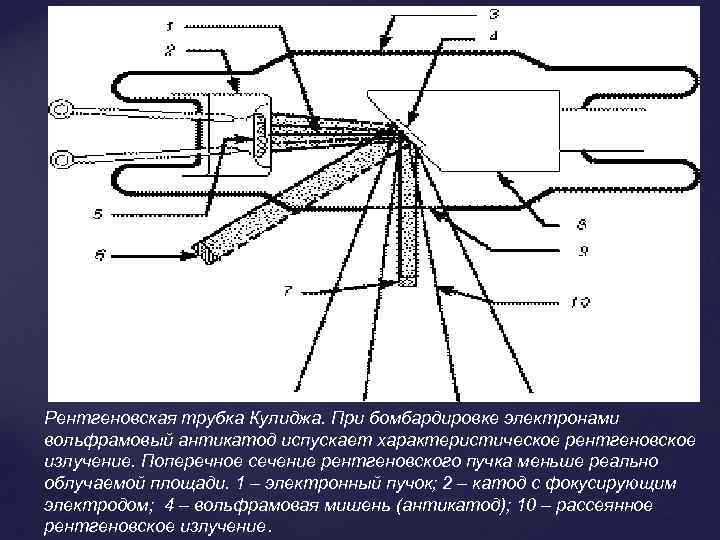

Рентгеновская трубка Кулиджа. При бомбардировке электронами вольфрамовый антикатод испускает характеристическое рентгеновское излучение. Поперечное сечение рентгеновского пучка меньше реально облучаемой площади. 1 – электронный пучок; 2 – катод с фокусирующим электродом; 4 – вольфрамовая мишень (антикатод); 10 – рассеянное рентгеновское излучение.

Рентгеновская трубка Кулиджа. При бомбардировке электронами вольфрамовый антикатод испускает характеристическое рентгеновское излучение. Поперечное сечение рентгеновского пучка меньше реально облучаемой площади. 1 – электронный пучок; 2 – катод с фокусирующим электродом; 4 – вольфрамовая мишень (антикатод); 10 – рассеянное рентгеновское излучение.